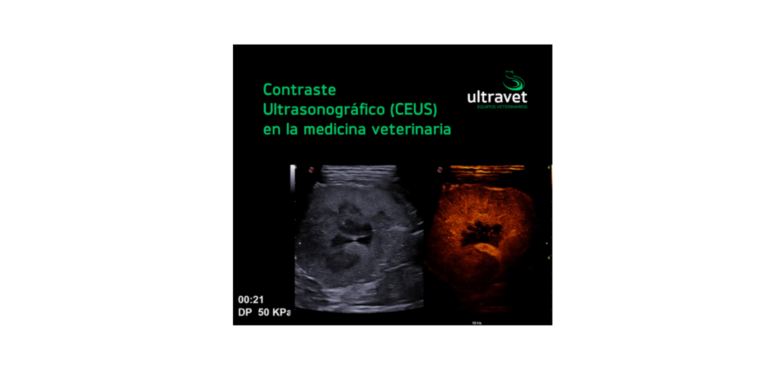

Contraste Ultrasonográfico (CEUS) en la medicina veterinaria: transformando diagnósticos con precisión y seguridad

Contraste Ultrasonográfico (CEUS) en la medicina veterinaria: transformando diagnósticos con precisión y seguridad    En el ámbito de la medicina…